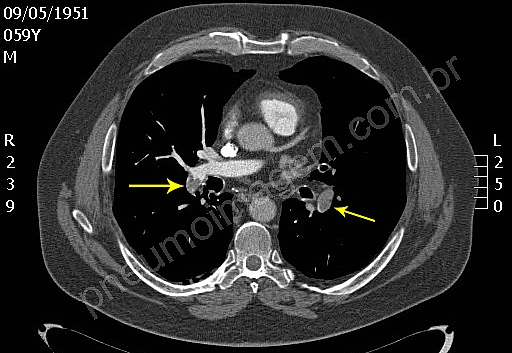

3- Para Tromboembolia Pulmonar (TEP) subsegmentar, isolada, de baixo risco, é recomendada a vigilância clínica, em vez de anticoagulação.